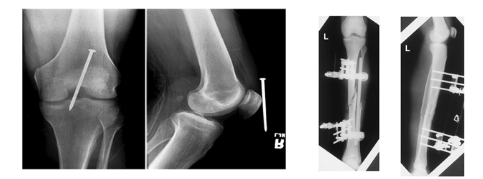

MINIMUM TWO VIEWS/PROJECTIONS

Anatomic structures superimposed ( Placed or laid on top of each other)

Localization of lesions or foreign bodies ( For example the nail near the knee)

Determination of alignment of fractures ( For example: the alignment of the tibia )

1 x-ray done straight on ( PA or AP) → Nail seems deep

1 x-ray 90 degree from that projection for true lateral → Nail adjacent to knee after true lateral

Positioning Rules and Principles

MINIMUM THREE PROJECTIONS/VIEWS

when joints are in prime interest area

AP or PA

Lateral

Oblique

Joints in a prime interest area how many projections?

Three